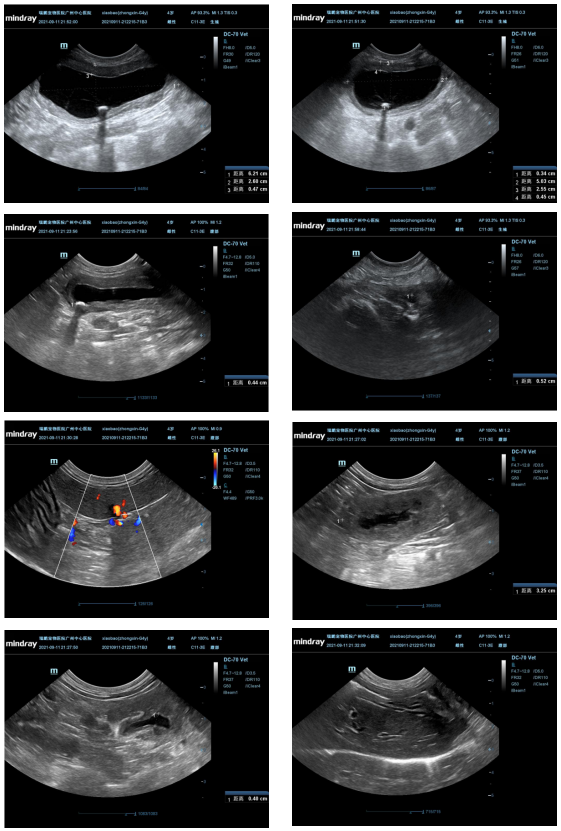

(2)超声检查:

点击查看超声检查图像

超声提示:

1. 左侧肾脏体积偏小,边缘不平滑,实质钙化灶,肾盂少量积液,输尿管回声降低,疑似慢性肾病、输尿管损伤或输尿管炎;右肾稍肥厚,肾盂积液,疑似慢性肾病。

2.膀胱中度充盈,膀胱壁回声增高,疑似膀胱炎;膀胱受重侧可见沉积颗粒,疑似膀胱结石(长径约 0.44cm);尿道回声降低,疑似尿道炎或尿道损伤。

3.肝脏回声降低,疑似肝炎。

4.胆汁淤积。

5.左侧肾脏周围少量积液。